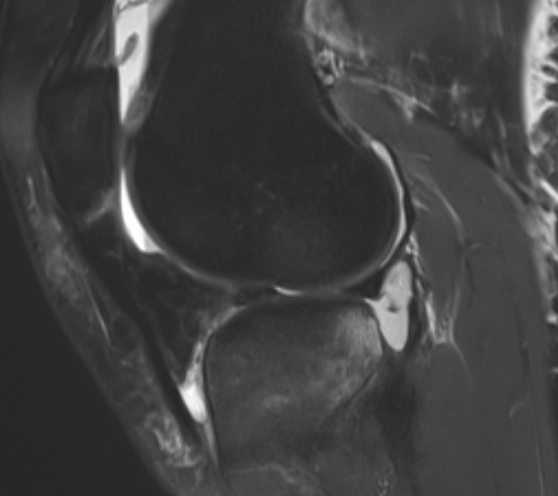

3. Meniscocapsular ligament tear